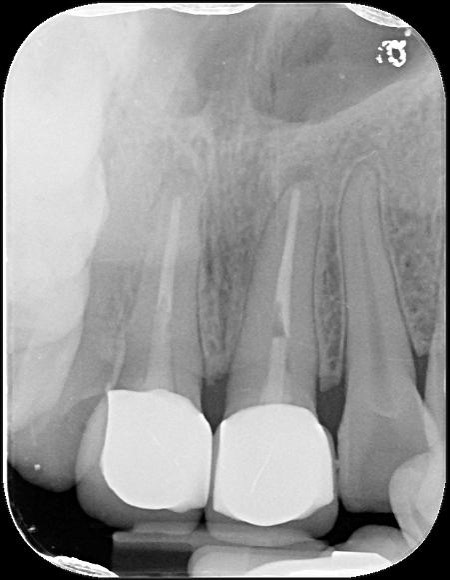

治療後根尖片,密合度良好